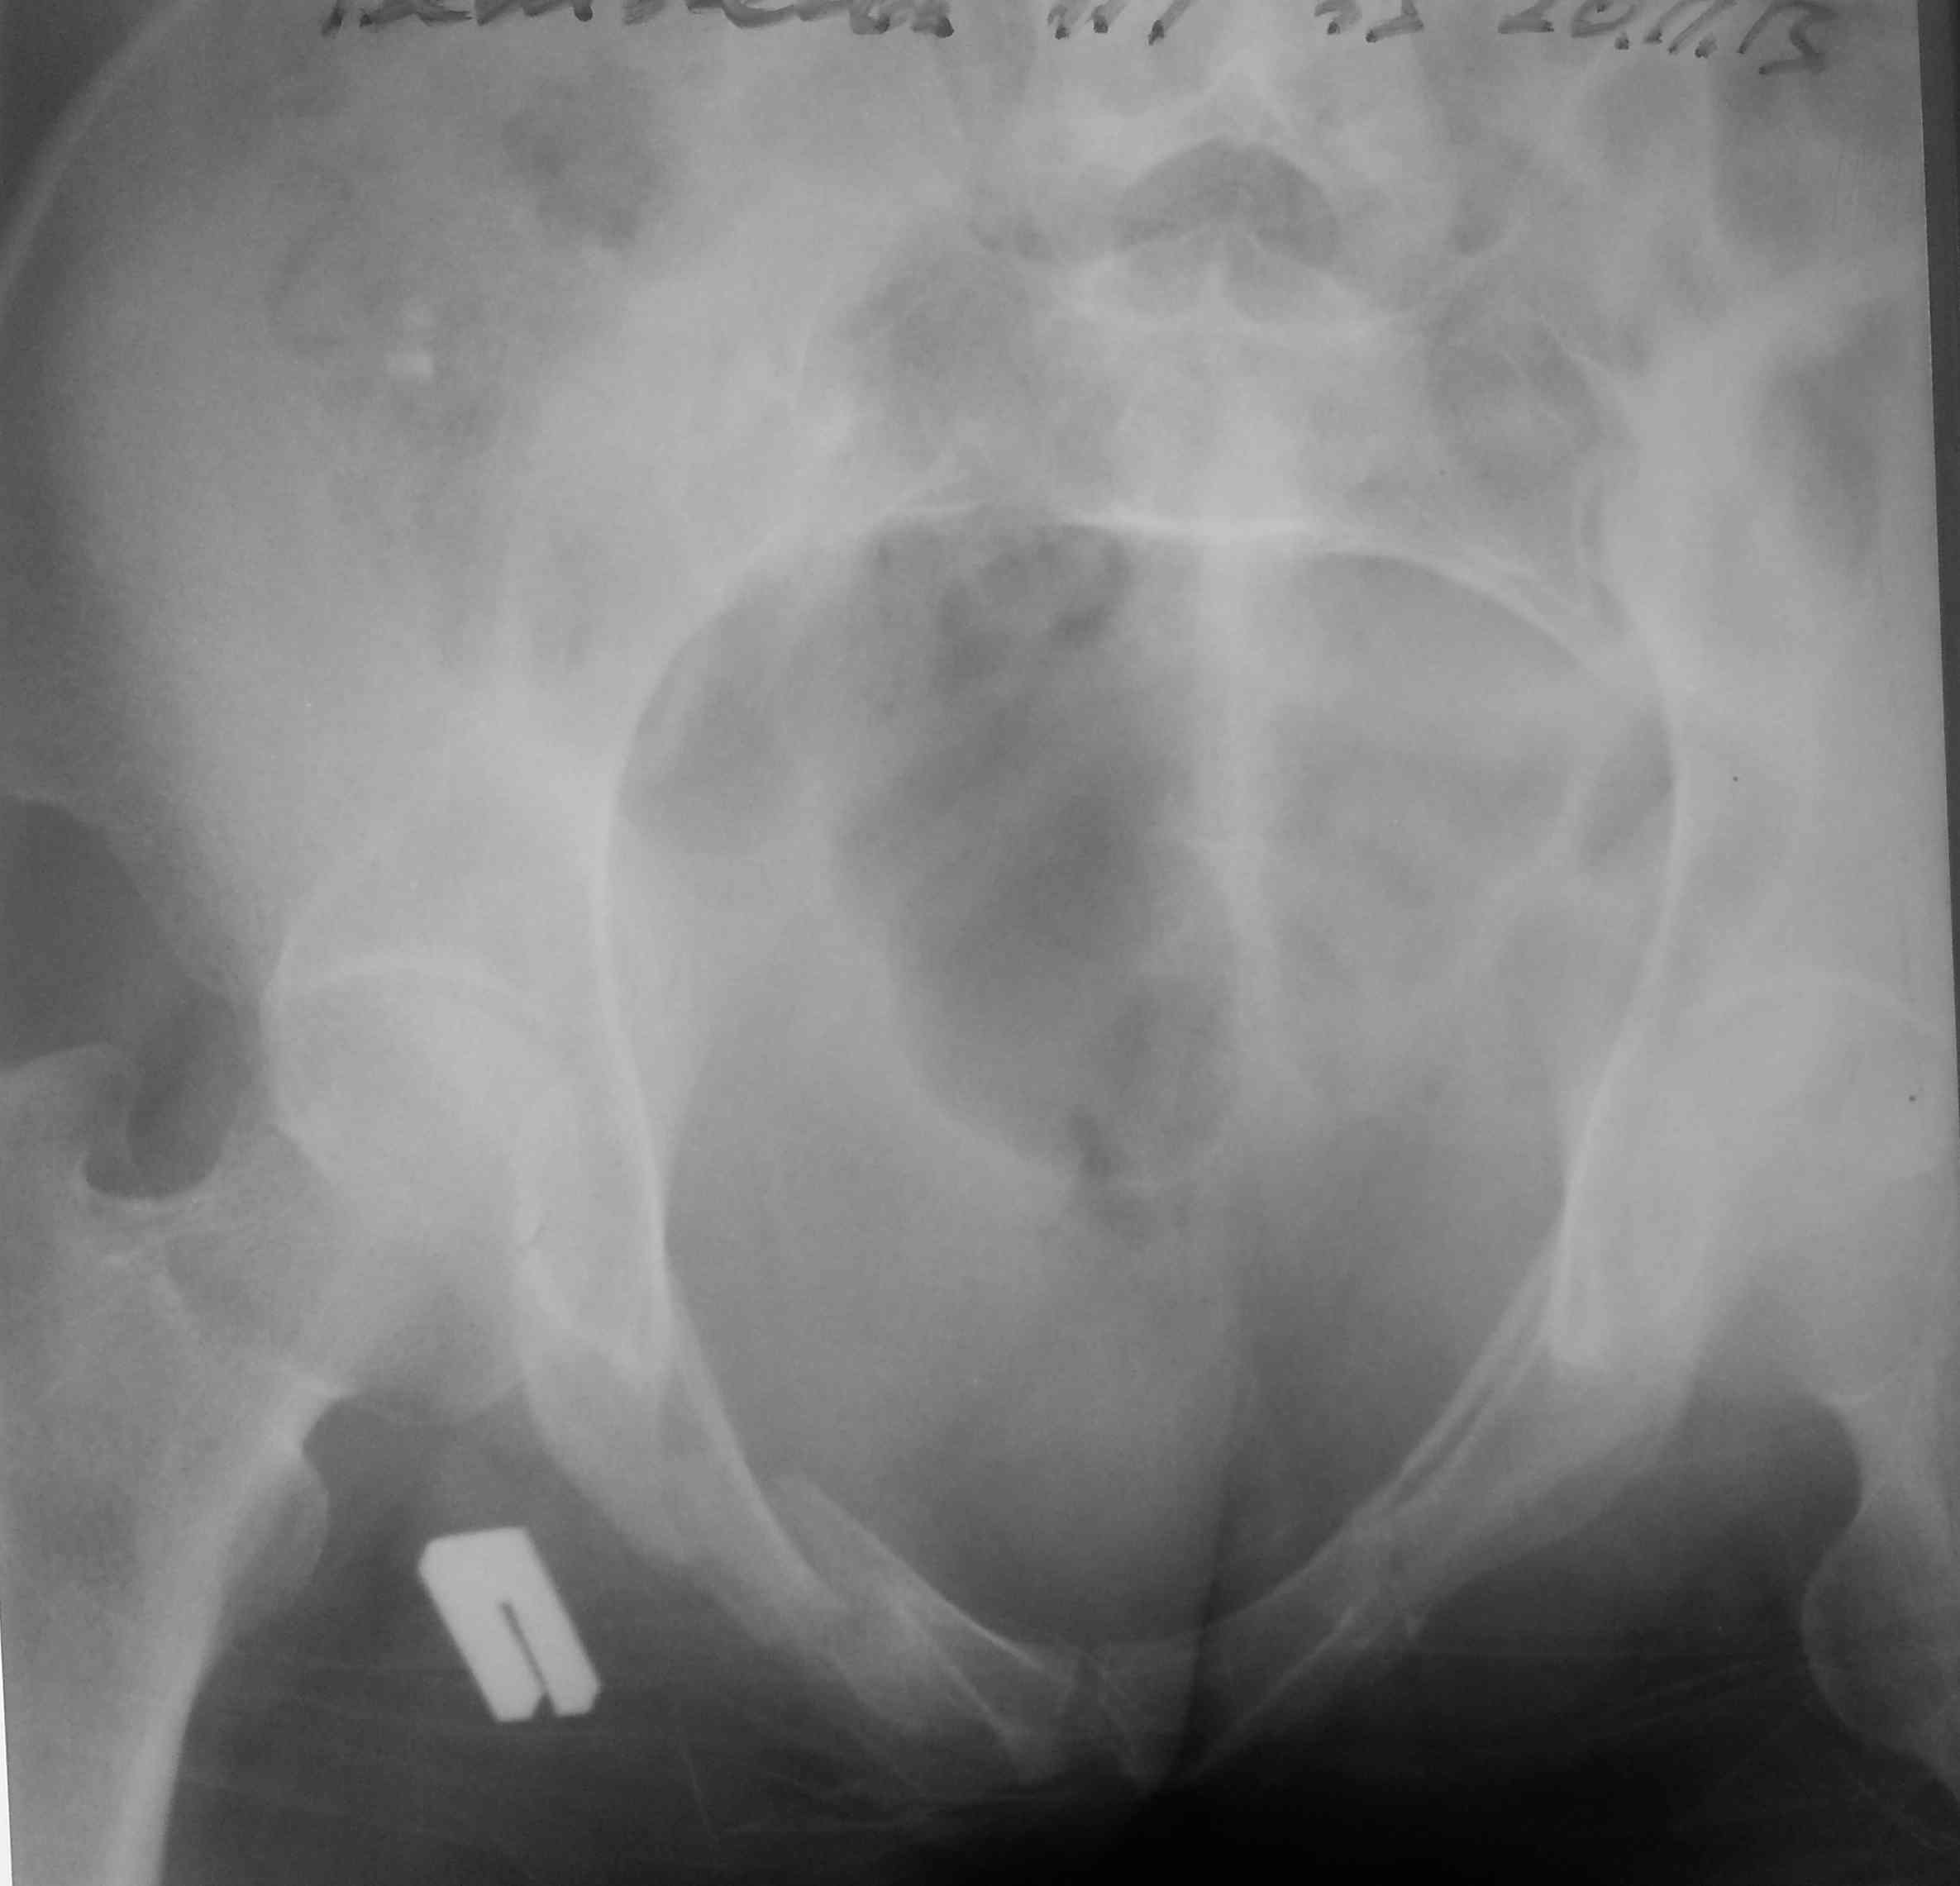

[Ortho] тяжелый таз

высылаю контрольные снимки на вытяжении, правую половину таза

подрепонировали вручную, за лево - скелетка. Дополнительно, левое плечо

- диафиз, множественные переломы ребер слева. Стала хуже по легким. Пока

план - при улучшении по легким - передняя рама + илиосакральные винты

справа, при улучшении - расслабляем переднюю раму, открыто синтезируем

подвздошную кость задним доступом, обратно затягиваем аппарат. Плечо -

когда получится